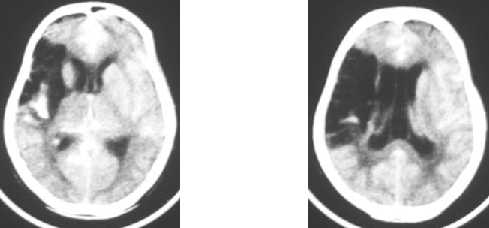

Ischemic brain diseases : cerebral nfarct - MCA